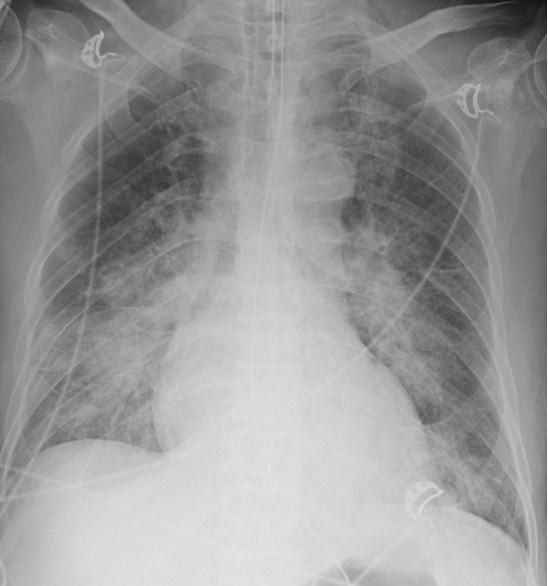

This 74-year-old male smoker with coronary artery disease presented with intermittent fever, abdominal pain and vomiting for a whole. Pulmonary infection related 2nd myocardial infarction was considered as first impression due to pulmonary edema related respiratory failure by CXR and ST elevation atlead V2-3 on ECG. However, ischemic heart disease could not be exculded due to reduced left ventricular ejectional fraction detected. No specific findings were noted on physical examination.

Relevant Test Results Prior to Catheterization

Theseries tests were provided on him prior to catheterization including laboratorytest, chest X-ray, and echocardiography. Mild elevation of cardiac enzymes andmild pulmonary edema were presented. The echocardiography showed 35% of leftventricular ejection fraction with hypokinesia of left ventricular basalinferior wall, apex, and mid-to-apical anterior wall. The rest of tests were unremarkable.